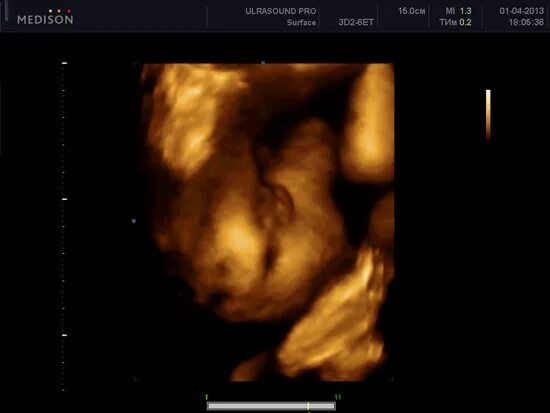

16 неделя можно ли узнать пол ребенка